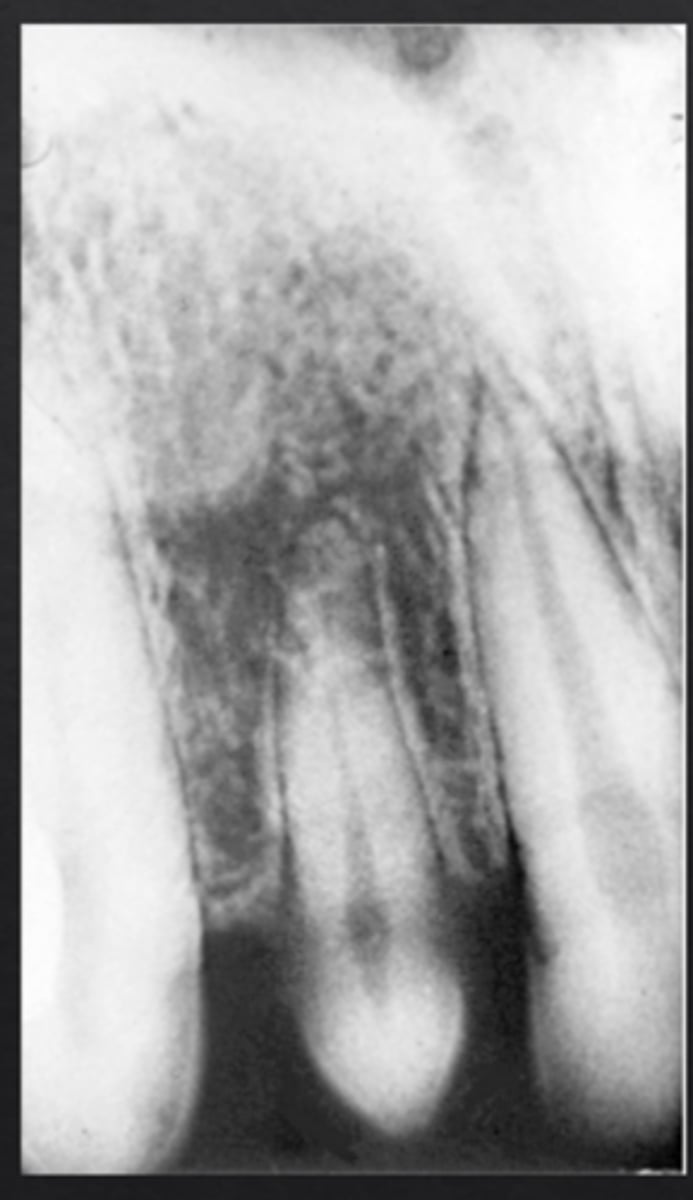

What is dens invaginatus (dens in dente)?

Infolding of enamel into the tooth, forming "tooth within a tooth"

Which tooth is most commonly affected by dens invaginatus?

Maxillary lateral incisors